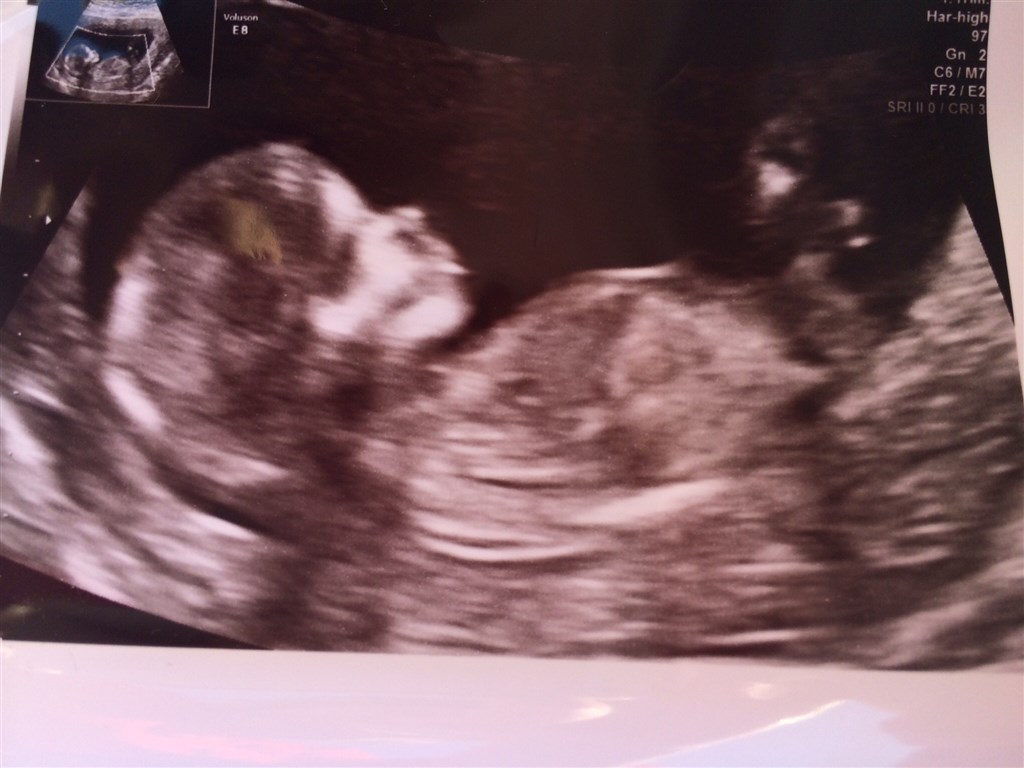

Så var kæresten og jeg til nakkefoldsscanning i tirsdags. Alt så rigtig godt ud og så ud som det skal, med en risiko der siger 1:17888

Bebs blev skønnet til 6,5 cm og det var HELT uvirkeligt at se den lille!! Min kæreste kneb en lille tåre

En lille update herfra og i snydes selvfølgelig ikke for et billede af bebs